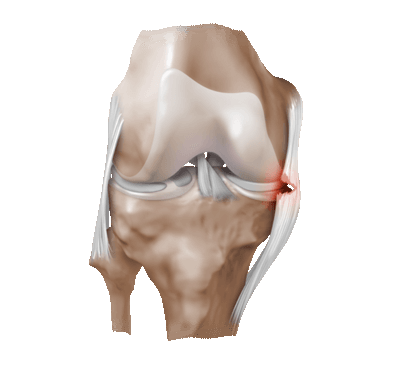

Частичный надрыв боковой связки коленного сустава.

После травмы может возникнуть нестабильность коленного сустава как следствие разрыва одной или нескольких связок. Наиболее часто оперативное вмешательство выполняется по поводу разрыва передней крестообразной связки. Но в ряде случаев происходит разрыв задней крестообразной связки, наружной и внутренней коллатеральной связки, связочного аппарата задне-латерального отдела коленного сустава, связочного аппарата поддерживающего надколенник и ряд других повреждений. Восстановление связок производится при помощи собственного аллотрансплантатов (например, собственных полусухожильной и нежной мышц), а также трупных связок и синтетических аналогов. Сами операции технически довольно сложные вмешательства, по этой причине они будут рассмортены в отдельных статьях.